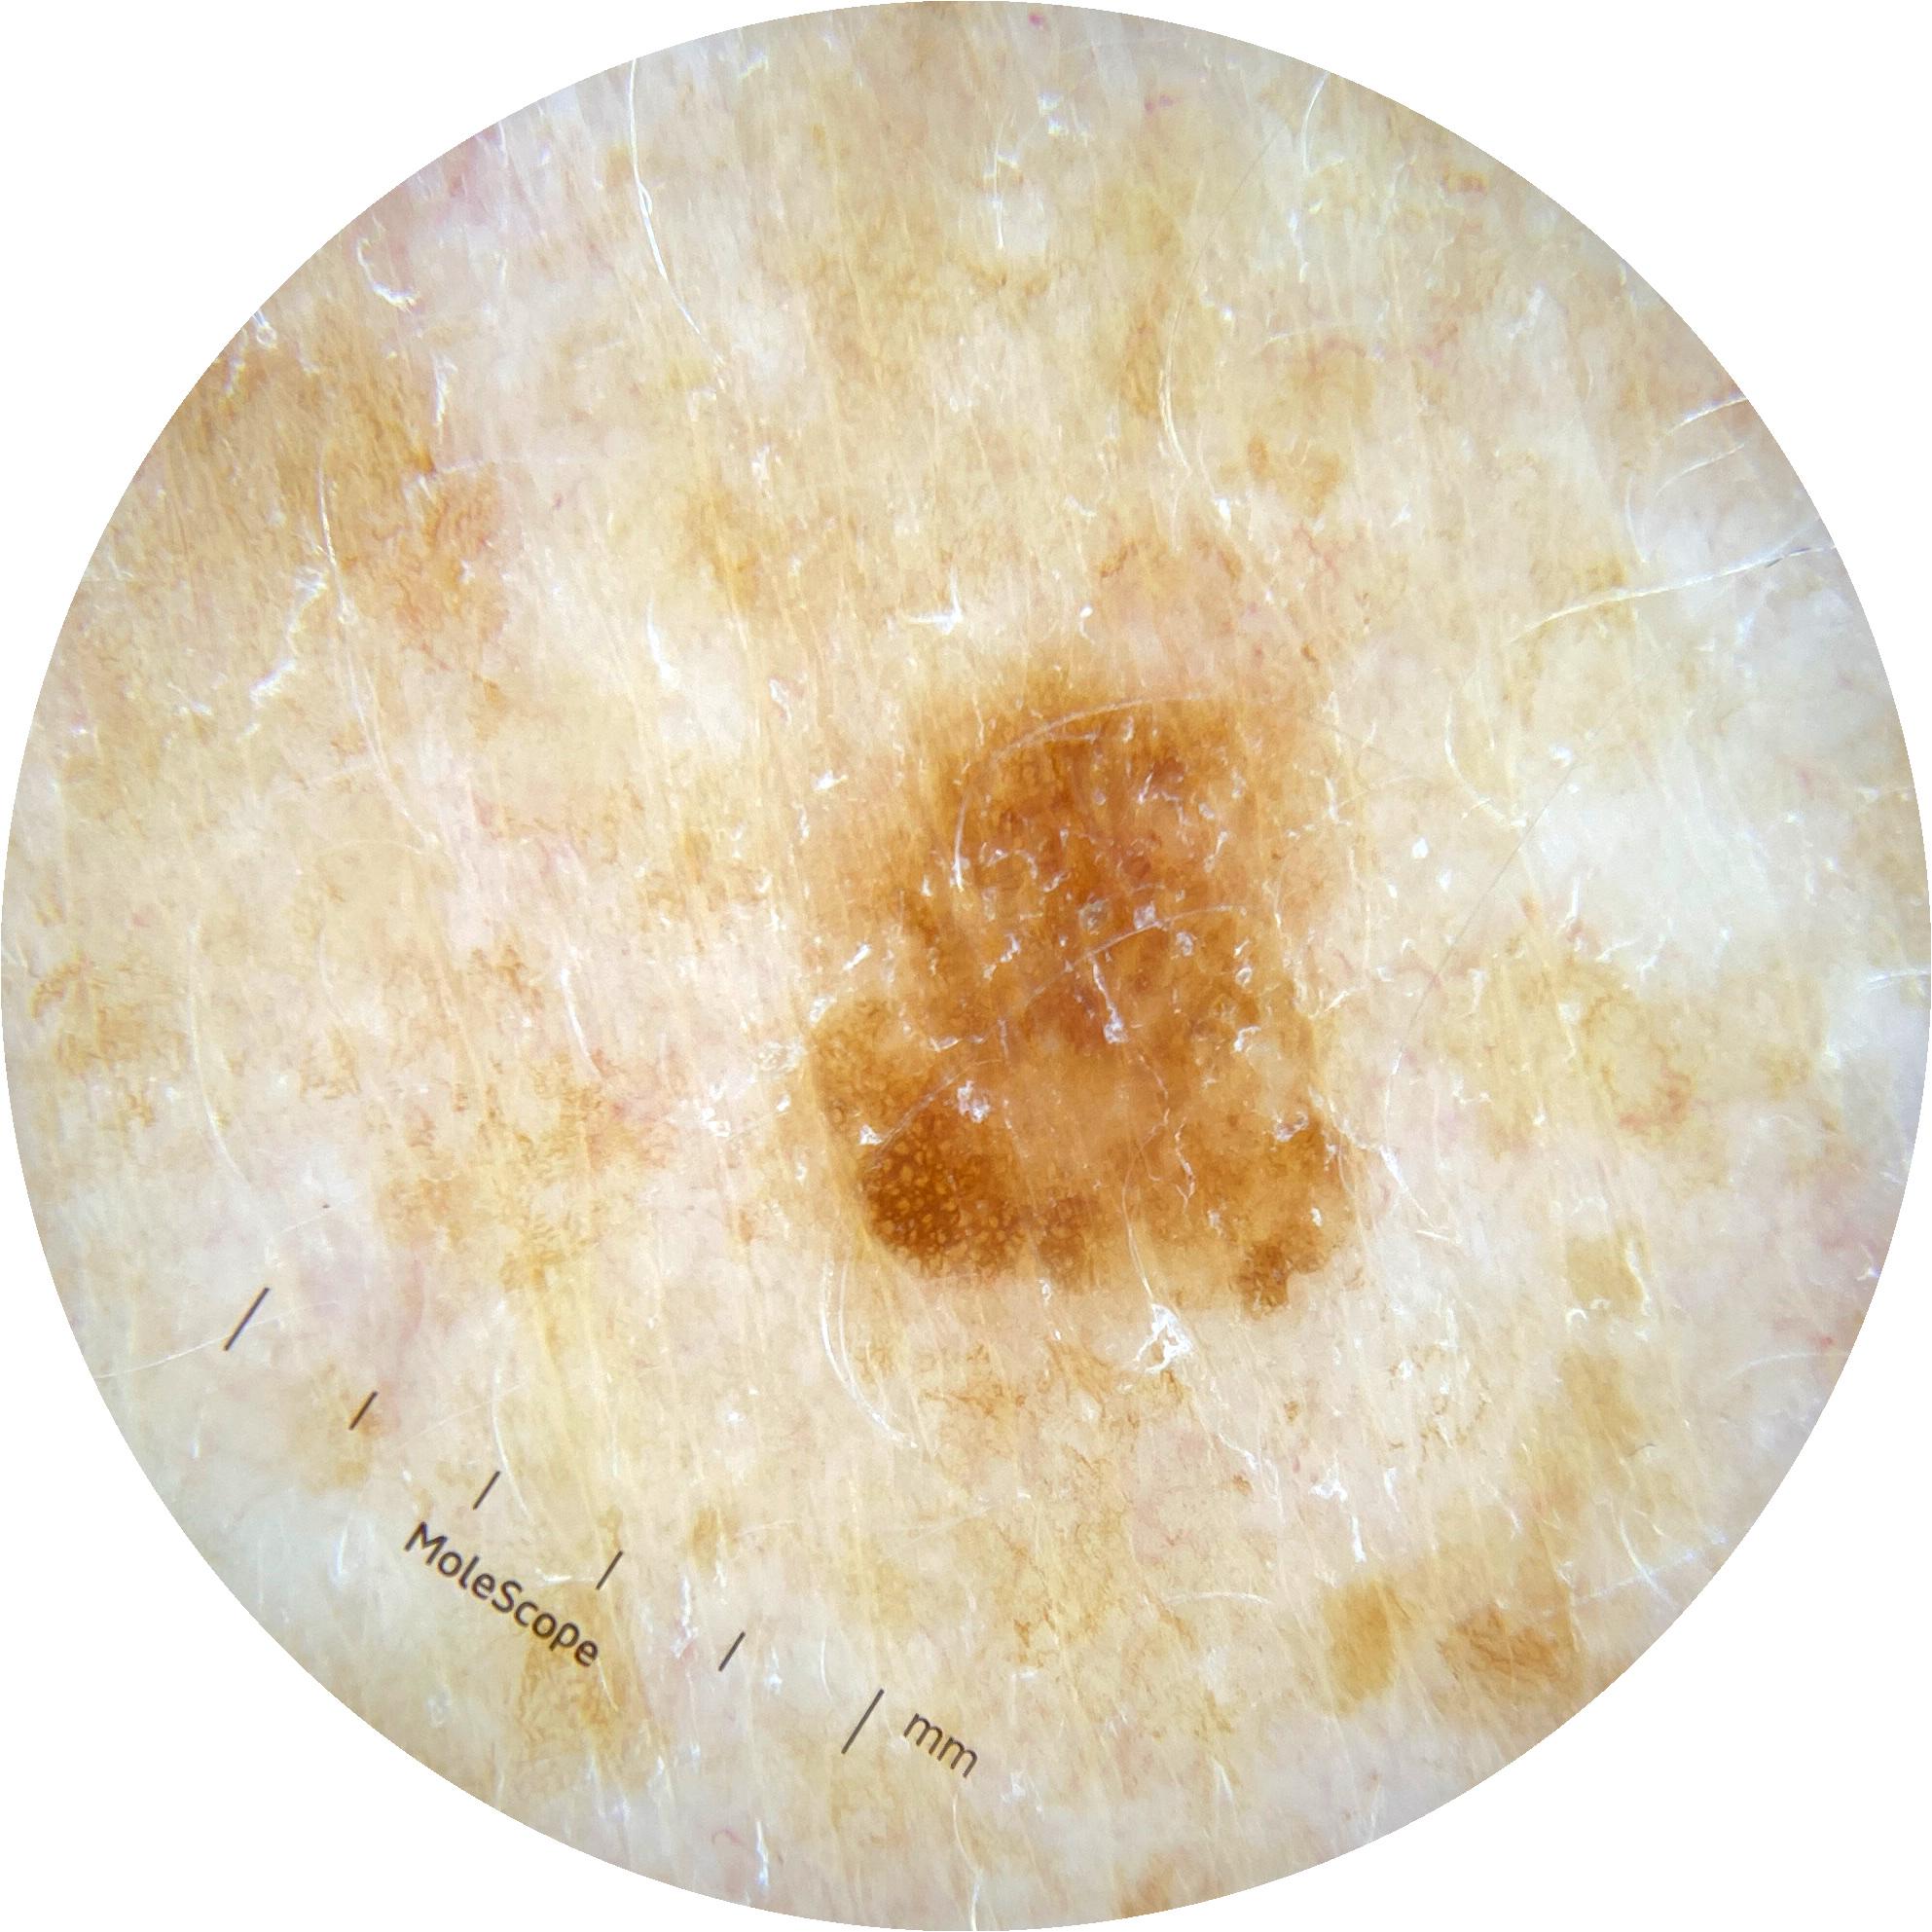

ISIC_5873799

2041 x 2041

acquisition_day 102

age_approx 65

anatom_site_1 Upper extremity

anatom_site_general upper extremity

diagnosis_1 Benign

diagnosis_confirm_type single image expert consensus

fitzpatrick_skin_type III

image_type dermoscopic